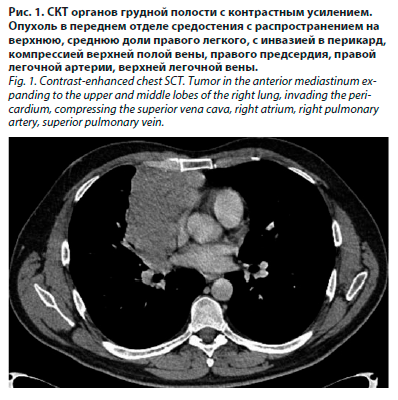

В микробиологическом анализе мокроты обнаружен рост золотистого стафилококка в титре, близком к диагностическому. При контрольном КТ-исследовании обнаружены уменьшение размеров опухоли, появление интерстициальных изменений, участков консолидации легочной ткани в зонах облучения и жидкости в правой плевральной полости, что расценено как признаки лучевого плевропневмонита 2-й степени по шкале RTOG (рис. 2).

При формировании схемы лечебных мероприятий руководствовались принципами лечения лучевых повреждений легких, изложенными в патенте RU 2487706 [9]. Для применения в амбулаторных условиях был назначен комплекс противовоспалительных средств, включавший антибиотикотерапию с учетом чувствительности микрофлоры (цефтриаксон 2 г/сут в течение 10 дней), преднизолон в суточной дозе из расчета 1 мг/кг на 2 нед внутрь с постепенным снижением дозы, будесонид через небулайзер от 1000 мг/сут с дальнейшим снижением дозы, флуконазол, антигистаминные и отхаркивающие средства, омепразол, калия и магния аспарагинат. Через 1 мес состояние пациента стабилизировалось: нормализовалась температура тела, уменьшилась одышка, повысилась толерантность к физической нагрузке. Фиксировалась выраженная положительная динамика показателей воспаления. Динамика уровней лейкоцитов и тромбоцитов в клиническом анализе крови не была показательна вследствие химиолучевого лечения в анамнезе. Через 2 мес пациент жаловался на сердцебиение, боль в мышцах ног, одышку при нагрузках, сохранялись умеренная гипотензия и тахикардия, в легких аускультативно определялись немногочисленные сухие хрипы справа, дыхание проводилось во все отделы. В анализах крови фиксировалось снижение маркеров воспаления. При контрольном КТ-исследовании зафиксированы дальнейшее уменьшение размеров опухоли, регресс инфильтративных изменений в легочной ткани с появлением признаков фибротизации, отсутствие жидкости в правой плевральной полости (рис. 3).

Состояние лучевого повреждения легочной ткани расценивалось как соответствующее 1–2-й степени тяжести по шкале RTOG/EORTC. Учитывая положительный ответ опухоли на химиолучевое воздействие, на очередном онкологическом консилиуме принято решение о хирургическом вмешательстве. В сентябре 2023 г. в МРНЦ выполнены стерноторакотомия справа, удаление опухоли средостения с резекцией и пластикой перикарда, резекцией правого диафрагмального нерва, верхняя и средняя лобэктомия с апикальной плеврэктомией, прецизионное удаление образований париетальной плевры. На 5-е сутки после операции у пациента повысилась температура тела до 39 ºС с ознобом, в анализах крови повысились уровни лейкоцитов и С-реактивного белка, зафиксирован палочкоядерный сдвиг (см. таблицу), состояние было расценено как нозокомиальная пневмония в раннем послеоперационном периоде, что было подтверждено с помощью СКТ (рис. 4).

С учетом спектра персистирующей в стационаре флоры назначенный ранее цефтриаксон был заменен на пиперациллин/тазобактам в дозе 4,5 г 4 раза в сутки с положительным эффектом в виде нормализации температуры тела, улучшения общего состояния, снижения острофазовых показателей. На 12-е сутки после операции пациент был выписан в удовлетворительном состоянии с рекомендациями приема в амбулаторных условиях комбинации ципрофлоксацин/амоксиклав в течение 5 дней, к лечению добавлен дексаметазон коротким курсом с дальнейшим переходом на метилпреднизолон и будесонид по прежней схеме в течение 1 мес со снижением дозы до отмены обоих препаратов на фоне применения бронхолитических и отхаркивающих средств. Через 3 мес после операции (декабрь 2023 г.) на СКТ в паренхиме нижней доли правого легкого определялись участки фиброза, в плевральной полости – стабильный гидроторакс (рис. 5).

В дальнейшем, в результате ухудшения на фоне острой респираторной вирусной инфекции, была проведена противовоспалительная терапия, включавшая короткий курс системных и топических глюкокортикостероидов (ГКС), антибиотика, бронхо- и муколитиков. Из побочных эффектов противовоспалительной терапии имела место гастропатия, купированная приемом ингибиторов протонной помпы, и кратковременная гипокалиемия, регрессировавшая после отмены ГКС. В настоящее время пациент стабилен; одышка возникает при подъеме на 4-й этаж; дыхание в легких везикулярное, ослаблено в нижних отделах справа, на форсированном выдохе – единичные сухие проводные хрипы; показатели крови в пределах нормы; постоянно получает спирива респимат в соответствии с данными спирографии. Выполняет домашнюю работу, трудится по специальности, находится под наблюдением онколога. При анализе данных СКТ в динамике выявлен рост опухолевых образований по париетальной плевре справа при стабилизации лучевых, послеоперационных и поствоспалительных изменений (рис. 6).